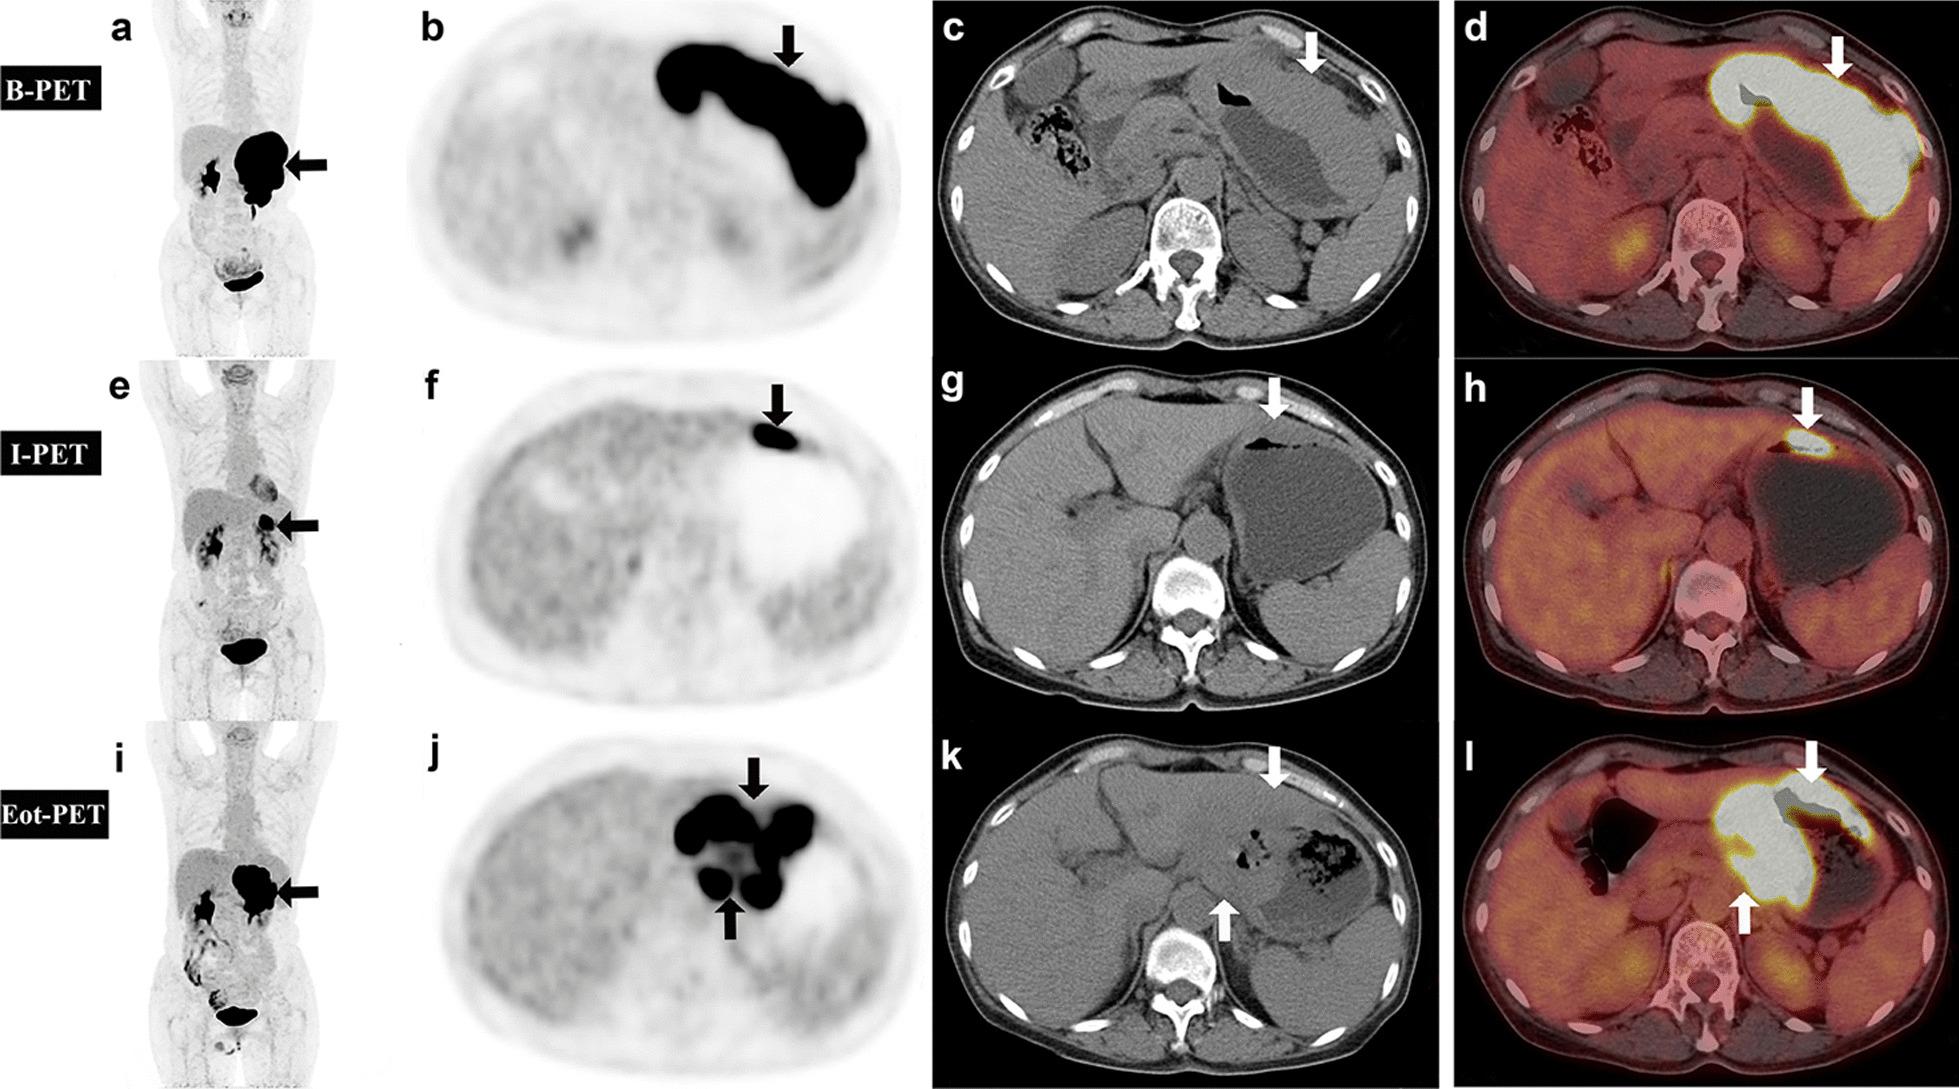

In the present study, we aimed to investigate the role of baseline (B), interim (I) and end-of-treatment (Eot) F-FDG PET/CT in assessing the prognosis of diffuse large B cell lymphoma (DLBCL), so as to identify patients who need intensive treatment at an early stage.

A total of 127 DLBCL patients (62 men; 65 women; median age 62 years) were retrospectively analyzed in this study. Baseline (n = 127), interim (n = 127, after 3-4 cycles) and end-of-treatment (n = 53, after 6-8 cycles) PET/CT images were re-evaluated; semi-quantitative parameters such as maximum standardized uptake value of lesion-to-liver ratio (SUVmax) and lesion-to-mediastinum ratio (SUVmax), total metabolic tumor volume (TMTV) and total metabolic tumor volume (TLG) were recorded. ΔTLG was the change of interim relative to baseline TLG (I to B), ΔTLG (Eot to B). ΔSUVmax and ΔTMTV were the same algorithm. The visual Deauville 5-point scale (D-5PS) has been adopted as the major criterion for PET evaluation. Visual analysis (VA) and semi-quantitative parameters were assessed for the ability to predict progression-free survival (PFS) and overall survival (OS) by using Kaplan-Meier method, cox regression and logistic regression analysis. When visual and semi-quantitative analysis are combined, the result is only positive if both are positive.

At a median follow-up of 34 months, the median PFS and OS were 20 and 32 months. The survival curve analysis showed that advanced stage and IPI score with poor prognosis, ΔSUVmax < 89.2%, ΔTMTV < 91.8% and ΔTLG < 98.8%, ΔSUVmax < 86.4% were significantly related to the shortening of PFS in patient (p < 0.05). ΔSUVmax < 83.2% and ΔTLG < 97.6% were significantly correlated with the shortening of OS in patients (p < 0.05). Visual analysis showed that incomplete metabolic remission at I-PET and Eot-PET increased the risk of progress and death. In terms of predicting recurrence by I-PET, the combination of visual and semi-quantitative parameters showed higher positive predictive value (PPV) and specificity than a single index.

Three to four cycles of R-CHOP treatment may be a time point for early prediction of early recurrence/refractory (R/R) patients and active preemptive treatment. Combined visual analysis with semi-quantitative parameters of F-FDG PET/CT at interim can improve prognostic accuracy and may allow for more precise screening of patients requiring early intensive therapy.

在本研究中,我们旨在探讨基线(B)、中期(I)和治疗结束时(Eot)的F-FDG PET/CT在评估弥漫性大B细胞淋巴瘤(DLBCL)预后中的作用,以便识别需要早期强化治疗的患者。

本研究回顾性分析了127例DLBCL患者(62例男性;65例女性;中位年龄62岁)。重新评估了基线(n = 127)、中期(n = 127,3 - 4个周期后)和治疗结束时(n = 53,6 - 8个周期后)的PET/CT图像;记录了半定量参数,如病变与肝脏比值的最大标准化摄取值(SUVmax)、病变与纵隔比值(SUVmax)、总代谢肿瘤体积(TMTV)和总代谢肿瘤负荷(TLG)。ΔTLG是中期相对于基线TLG(I相对于B)、ΔTLG(Eot相对于B)的变化。ΔSUVmax和ΔTMTV采用相同算法。视觉Deauville 5分法(D-5PS)已被用作PET评估的主要标准。采用Kaplan-Meier法、cox回归和逻辑回归分析评估视觉分析(VA)和半定量参数预测无进展生存期(PFS)和总生存期(OS)的能力。当视觉分析和半定量分析相结合时,只有两者均为阳性结果才为阳性。

中位随访34个月时,中位PFS和OS分别为20个月和32个月。生存曲线分析表明,晚期和预后不良的国际预后指数(IPI)评分、ΔSUVmax < 89.2%、ΔTMTV < 91.8%和ΔTLG < 98.8%、ΔSUVmax < 86.4%与患者PFS缩短显著相关(p < 0.05)。ΔSUVmax < 83.2%和ΔTLG < 97.6%与患者OS缩短显著相关(p < 0.05)。视觉分析显示,I-PET和Eot-PET时代谢未完全缓解增加了进展和死亡风险。在通过I-PET预测复发方面,视觉和半定量参数相结合显示出比单一指标更高的阳性预测值(PPV)和特异性。

三到四个周期的R-CHOP治疗可能是早期预测早期复发/难治(R/R)患者并进行积极抢先治疗的时间点。中期将视觉分析与F-FDG PET/CT的半定量参数相结合可提高预后准确性,并可能允许更精确地筛选需要早期强化治疗的患者。